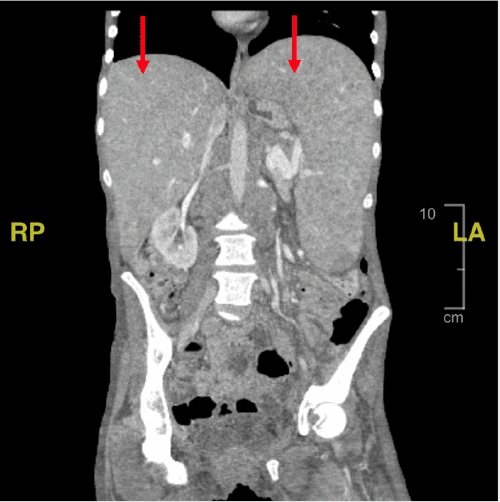

A CT scan of the abdomen (Figure 1) demonstrated marked hepatosplenomegaly (spleen measuring 23 × 15 × 9 cm) and retroperitoneal and mesenteric lymphadenopathy. The differential diagnosis included metastatic lymphoma, disseminated Mycobacterium avium-intracellulare complex (MAC), Castleman disease, and tuberculosis. The patient was started on PCP prophylaxis (atovaquone) and broad-spectrum antibiotics (vancomycin and cefepime). Cardiology was consulted, and a transthoracic echocardiogram showed no acute abnormalities. A multidisciplinary team (hematology/oncology, infectious disease, internal medicine, and general surgery) recommended splenectomy for both diagnostic and therapeutic purposes.

Figure 1. Abdominal and Pelvic CT Imaging with IV Contrast. Published with Permission

(A) Axial view demonstrating hepatosplenomegaly. The spleen measures approximately 23 × 15 × 9 cm at its largest dimensions

(B) Coronal view confirming hepatosplenomegaly.

CT findings in disseminated MAC often include marked hepatomegaly, splenomegaly, multiple intra-abdominal lymph nodes larger than 10mm in diameter, and jejunal wall thickening.5 Nyberg et al. reported that 84% of patients with disseminated MAC have CT findings of large, bulky retroperitoneal and mesenteric lymphadenopathy, with often normally-sized peripheral lymph nodes.11 Our patient's CT scan demonstrated both hepatosplenomegaly and mesenteric and retroperitoneal lymphadenopathy. Furthermore, a significant proportion of patients with disseminated MAC have a history of at least one prior AIDS-defining illness, such as Kaposi sarcoma, lymphoma, Pneumocystis carinii pneumonia, cytomegalovirus infection, esophageal candidiasis, toxoplasmosis, or cryptosporidiosis.5